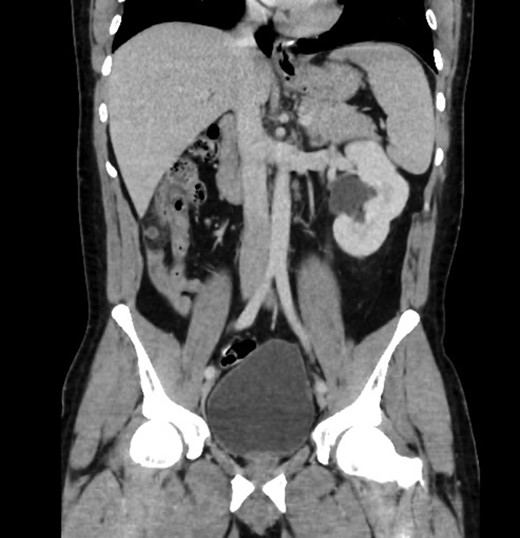

Upon review and clinically examination, the possibility of atypical appendicitis was raised due to the clinical history. Patient did not have any history of biliary colic or any epigastric pain. He was further investigated with CT abdomen which revealed the diagnosis of acute appendicitis in the right upper quadrant (Fig. 1). The atypical position of his presentation was a result of congenital right renal agenesis (Fig. 2). The appendix was lying on the right upper quadrant due to the absence of right kidney. He also had left kidney hydronephrosis and hypertrophy.

Axial view showing absence of right kidney due to congenital agenesis. Appendicitis with faecolith.